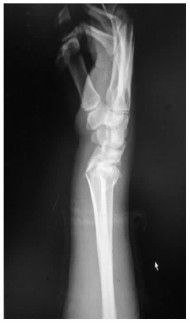

1.2 治疗方法急诊予以常规患侧腕关节正侧位X线片,必要时CT三维重建(图 1、2)。均采用臂丛麻醉,仰卧位,常规消毒铺巾,止血带止血。开放者直视下克氏针穿针固定,闭合骨折由助手牵引,手法复位纠正侧方移位,成角及短缩畸形,术中X线透视,骨折块或关节面复位不满意可借助克氏针撬拨复位或有限切开复位,复位满意后用多枚克氏针交叉固定。克氏针以刚穿出骨皮质为宜,以增加牢度,克氏针尾部折弯留于皮外,骨折初步复位后予以安装动力型外固定架,选择超关节外固定架,先于第二掌骨背外侧作2个0.5 cm切口,间距以外固定架钉夹为准,平行植入2枚2.5 mm支架螺钉,在距桡骨骨折线4~6 cm桡骨上置入2枚支架螺钉,安装并调整外固定架,保证远端球形活动关节位于桡腕关节水平线上,利于早期功能锻炼,同时调整外固定架施以适当牵引力,保持腕关节轻度尺偏掌曲位并锁紧,直至透视满意。术后第2天开始手指伸屈曲能锻炼,术后第1天,4周,6周、8周及3个月复查X线片(图 3、4),4周松外固定架锁紧装置开始功能锻炼,4~6周拔除克氏针,6~8周拆除外固定架。

| 图 2 急诊侧位片 |